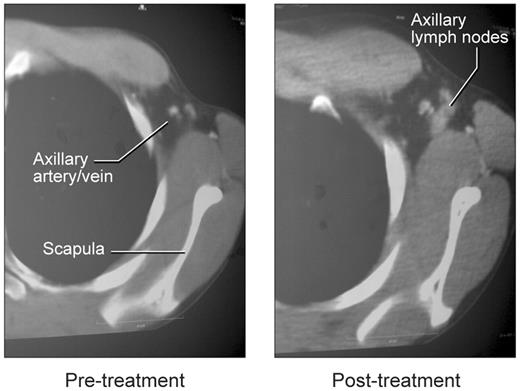

To assess the effect of rCD40L on lymph node architecture, we compared the histology of pretreatment and posttreatment tissue in one patient and examined posttreatment tissue in the other 2 patients (Figure 4). Before treatment, all 3 patients lacked palpable axillary lymph nodes, and little or no lymphoid tissue could be identified based on CT examination (Figure 5). One patient had an inguinal lymph node biopsy before rCD40L therapy that revealed small, scattered aggregates of IgM+/IgD+ B cells. However, no germinal centers were seen, and the B cells were primarily located in abortive follicles that contained only scant follicular dendritic cells. This histologic finding is similar to that described in previous studies of lymph nodes of XHM patients.8,34

Appearance of lymph nodes in left axilla with rCD40L treatment. Before treatment, the arrow indicates the location of the axillary artery and vein on contrast-enhanced CT studies. The image on the right shows emergence of axillary nodes.

A substantially different picture was obtained at the end of rCD40L treatment when all 3 patients had easily visualized lymph nodes on CT examination (Figure 5). These were particularly evident in the axillary areas, possibly because the majority of rCD40L injections were given in the forearm. Biopsy and histologic examination of these nodes revealed prominent cortical primary follicles associated with a robust development of follicular dendritic cells (Figure 4). However, as in the pretreatment specimen, no germinal centers were observed, and only IgM+/IgD+ B cells were present. There was no change in spleen size or in the number of circulating lymphocytes. Consistent with the lack of induction of germinal center development, the patients did not mount IgG responses to challenge with KLH or bacteriophage φX-174. Serum immunoglobulin levels were unchanged, and IgE as well as IgA levels remained below the level of detection (supplemental Table 3). Immunophenotyping studies before and after rCD40L treatment, revealed that all peripheral blood B cells remained invariably naive with surface coexpression of IgD and IgM. The failure of memory B-cell differentiation in these patients was further confirmed in 2 of the 3 patients with analysis of somatic mutations in the heavy chain V3-23 Ig V gene35 (supplemental Table 4). These results show that although in vivo rCD40L treatment at the dose level used in this study induces development of primary follicles and a follicular dendritic cell network, it does not result in the development of germinal centers or a further differentiation of naive B cells in the periphery.